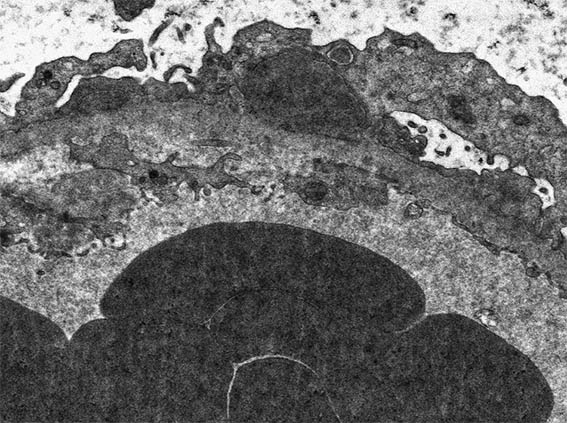

Figura 8. Microscopía electrónica, aumento original, X4.000. Observe depósitos electron-densos subepiteliales.

Figura 9. Microscopía electrónica, aumento original, X4.000. Observe el depósito grande, subepitelial, en la parte central de la imágen. ¿Recuerda cómo denominan a este tipo de depósito?